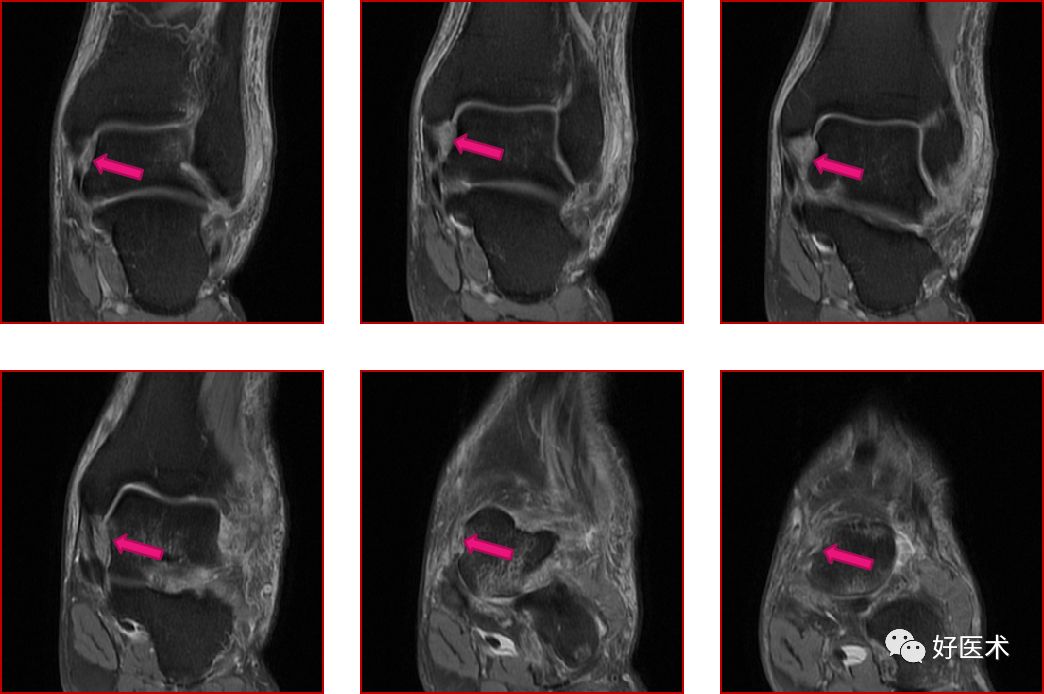

三、骨软骨病变

距骨骨软骨损伤,好发于前外侧、后内侧,尤其是后内侧,与内外翻损伤相关。

距骨骨软骨损伤分级

1度损伤:

2度损伤

3度损伤